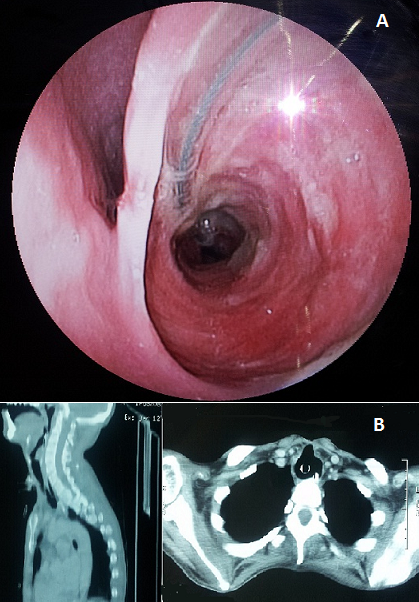

Patient âgé de 27 ans, hospitalisé au service de réanimation chirurgicale pour prise en charge d'un traumatisme crânien grave avec un score de Glasgow initiale à 4. Le patient était trachéotomisé à J6 de son admission. A j45, le patient commence à présenter des pneumopathies à répétitions et a bascule associé à la présence des débris alimentaires au niveau de liquide d'aspiration trachéale. Une fibroscopie œsophagienne, réalisée a objectivé une fistule oeso-trachéale (A), et le scanner thoracique a montré une large communication entre la paroi postéro-latérale gauche de la trachée et la lumière œsophagienne (B). La fistule œso-trachéale est une complication rare (incidence 0,5 %) de l'intubation trachéale prolongée. Les causes à l'origine de cette complication sont la lésion per opératoire de la paroi postérieure de la trachée, une mauvaise position de la canule notamment sa coudure, une mauvaise gestion du ballonnet en particulier des pressions, une sonde gastrique de gros calibre ou trop rigide, une infection fongique de l'œsophage et la dénutrition du patient. La prise en charge thérapeutique de ces patients va nécessiter, dans un premier temps, d'arrêter l'inhalation du liquide gastrique à travers la fistule et, de mettre au repos l'œsophage. Le traitement chirurgical est indiqué dans un 2ème temps. Les récidives sont possibles et la mortalité n'est pas négligeable (6,3 à12, 5%).